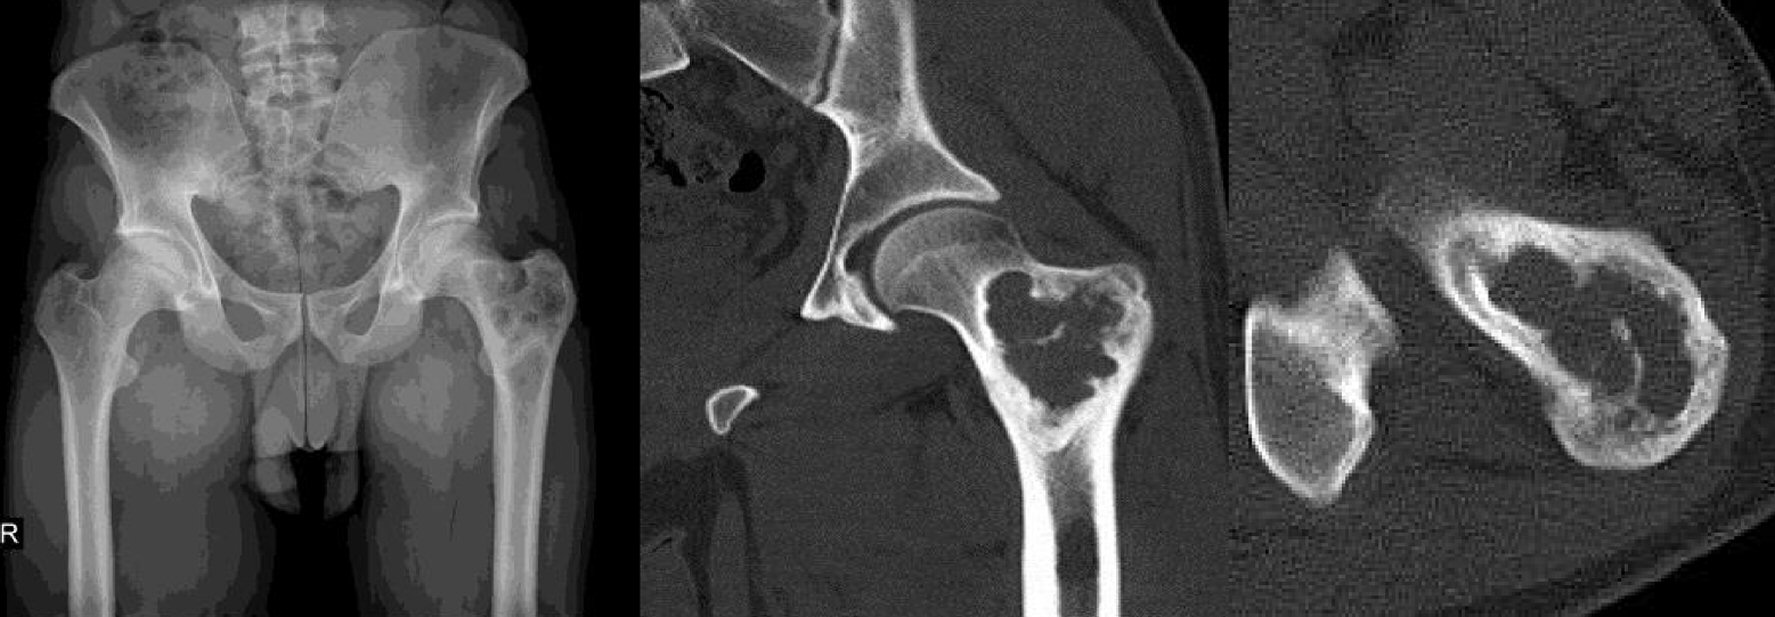

A 31-year-old man applied to our outpatient clinic with left hip pain that lasted for 6 months. In the X-ray examination, an expansile, multilobulated and cystic mass located in the proximal part of left femur was observed. The computed tomography (CT) examination revealed a multilobulated, lytic mass of 7 cm in diameter containing thin hyperdense septum extending to the greater trochanter and neck region, which was reported as a complicated cystic mass (Fig. 1).

![]() Click for large image | Figure 1. Preoperative X-ray and CT views of the mass. CT: computed tomography. |